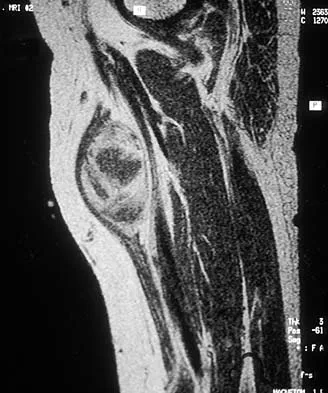

A 16-year-old girl has a painful foot mass. A radiograph, MRI scan, and biopsy specimens are shown in Figures 35a through 35d. What is the most likely diagnosis?

Explanation

Synovial sarcoma should always be considered in the differential diagnosis of a foot mass; however, the histopathology shows a typical example of PVNS, with hemosiderin, giant cells, and synovium. Synovial chondromatosis would have metaplastic cartilage in the synovium. The radiograph shows subtle erosion of the lateral cortex of the cuboid, and the MRI scan shows a soft-tissue mass. Ghert MA, Scully SP, Harrelson JM: Pigmented villonodular synovitis of the foot and ankle: A review of six cases. Foot Ankle Int 1999;20:326-330. Jones BC, Sundaram M, Kransdorf MJ: Synovial sarcoma: MR imaging findings in 34 patients. Am J Roentgenol 1993;161:827-830. Sartoris DJ, Resnick D: Magnetic resonance imaging of pediatric foot and ankle disorders. J Foot Surg 1990;29:489-494.

References:

- Scully SP, Temple HT, Harrelson JM: Synovial sarcoma of the foot and ankle. Clin Orthop 1999;364:220-226.